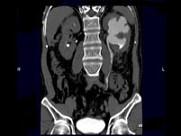

问题 男,58岁,尿频,尿痛伴低热乏力2月,CT如图所示,下列说法正确的是 ( )

选项 A.左侧肾盂肾盏扩张,其边缘不整 B.左侧输尿管多发性狭窄 C.左侧肾结核 D.左侧输尿管结核 E.左侧输尿管癌

答案 ABCD